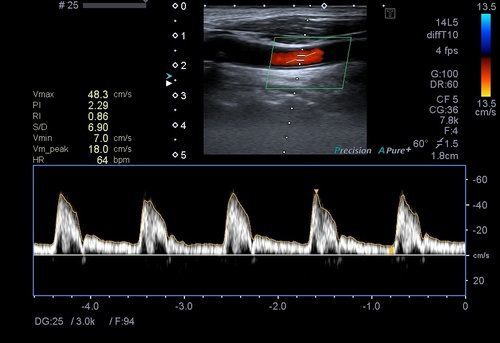

Karotis renkli doppler ultrason ile karotis damarımız (şah damarı) değerlendirilir. Bu damarda olası darlıklar, tıkanıklıklar, plaklar, balonlaşmalar (anevrizma) ve akım hızları-volümleri değerlendirilir. Bu damarlardaki problemler, beyni besleyen ana damarlar olduklarından hayati önem arz etmektedir.

Bu damarlarda tıkanıklıklar, balonlaşmalar (anevrizma), daralmalar ve akım hızları-volümleri değerlendirilir. Vertebral arterlerin oluşturduğu toplam debi yeterli düzeyin altında ise hastada vertigo oluşumuna sebep olabilir.